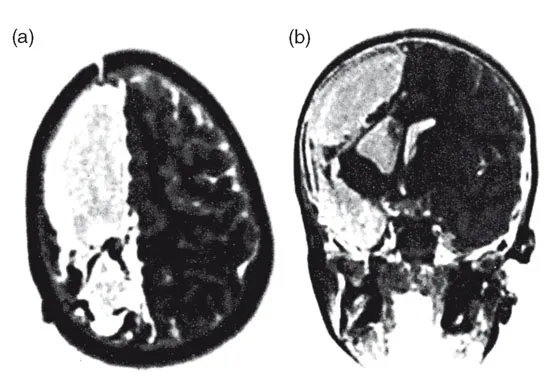

En dĂ©pit de son hĂ©miplĂ©gie gauche congĂ©nitale, Nico a rĂ©ussi Ă marcher avant lâĂąge de 1 an et 7 mois, et il a commencĂ© Ă faire des phrases un peu avant 2 ans. Il a eu ses deux premiĂšres crises dâĂ©pilepsie Ă 22 mois, mais elles ont complĂštement disparu pendant les huit mois qui ont suivi ; elles ont ensuite repris, accompagnĂ©es de convulsions et de pertes de conscience. Tout traitement mĂ©dical sâest avĂ©rĂ© inutile et lâĂ©pileptogĂ©nĂ©citĂ© a augmentĂ© de façon spectaculaire. Un EEG a confirmĂ© lâexistence dâun important foyer Ă©pileptique dans le cortex droit, impliquant les aires temporale, frontale et pariĂ©tale droites. Finalement, quand Nico a eu 3 ans et 7 mois, sa famille a dĂ©cidĂ© dâessayer un traitement neurochirurgical. Ă lâorigine, lâopĂ©ration devait se limiter Ă une rĂ©section du lobe temporal droit et Ă une dĂ©connexion du lobe frontal droit sous contrĂŽle cortigraphique. Mais aprĂšs cette premiĂšre procĂ©dure, la cortigraphie a continuĂ© Ă rĂ©vĂ©ler de multiples pics et dĂ©charges dans les aires droites restantes. Les mĂ©decins ont alors discutĂ© avec les parents de Nico des options qui se prĂ©sentaient, et ceux-ci ont acceptĂ© que lâon procĂšde Ă une hĂ©misphĂ©rectomie fonctionnelle. La technique appliquĂ©e dans ce cas consiste Ă supprimer la rĂ©gion corticale centrale, le cortex parasagittal et le gyrus cingulĂ©, et Ă pratiquer une lobectomie complĂšte, incluant lâamygdale et lâhippocampe. Les portions restantes du lobe frontal et des lobes pariĂ©to-occipitaux ont aussi Ă©tĂ© dĂ©connectĂ©es du tronc cĂ©rĂ©bral et de lâautre hĂ©misphĂšre. La pathologie mise au jour consistait en une polymicrogyrie des lobes temporal et pariĂ©tal droits avec une lĂ©gĂšre mĂ©ningite chronique. Nico sâest remarquablement rĂ©tabli. Les crises ont disparu, il nâa jamais perdu sa capacitĂ© de parler et a recommencĂ© Ă marcher au bout de quelques jours. Câest maintenant un enfant en bonne santĂ© et qui travaille bien Ă lâĂ©cole. Ce qui est surprenant, câest que, Ă voir son comportement, personne ne pourrait imaginer la quantitĂ© impressionnante de neurones quâil a perdue. En fait, si lâon nâa pas vu les images de son cerveau, il est impossible de croire quâil ne lui en reste que la moitiĂ©. La figure 1.1 montre une vue spectaculaire de cette hĂ©misphĂ©rectomie fonctionnelle droite.

Figure 1.1 â Deux images de lâhĂ©misphĂ©rectomie fonctionnelle droite (Nico, 3 ans et 7 mois) : (a) vue horizontale ; (b) vue frontale. On ne voit que lâhĂ©misphĂšre gauche, la plus grande partie de lâhĂ©misphĂšre droit a Ă©tĂ© retirĂ©e.